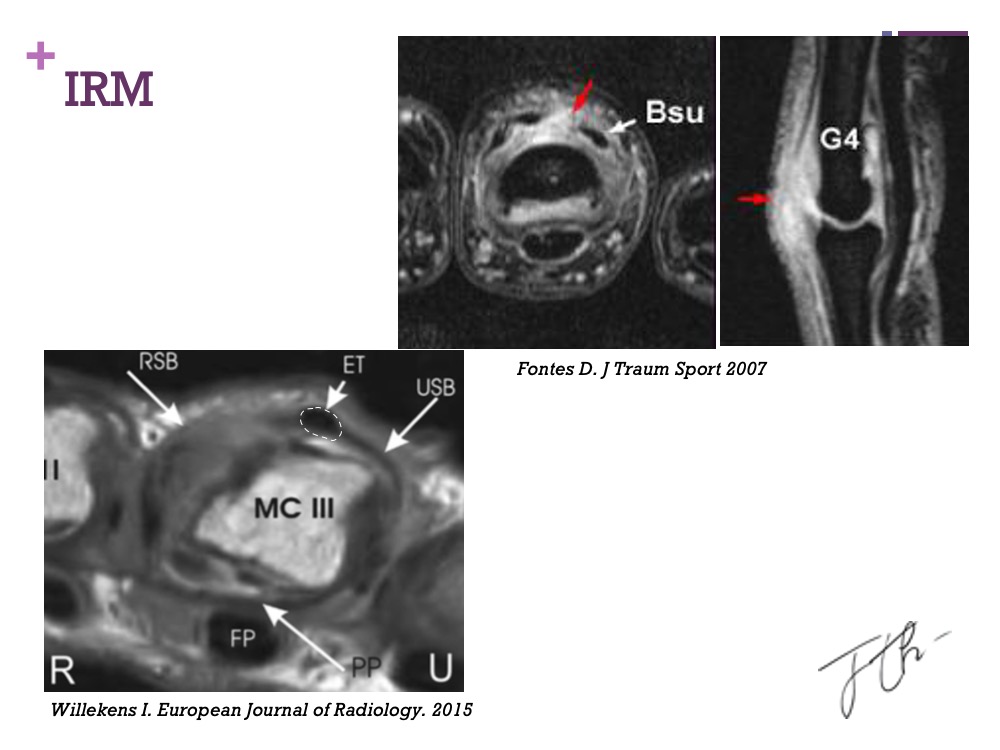

Les bandelettes sagittales constituent les principaux stabilisateurs de l’appareil extenseur au dos de la main. Leur lésion, également appelée « Boxer Knuckle », est souvent sous-diagnostiquée en raison de symptômes peu spécifiques. Il s’agit pourtant d’une atteinte fréquente, en particulier chez les sportifs pratiquant des disciplines de frappe comme la boxe.

Le diagnostic de cette pathologie reste difficile et nécessite une évaluation clinique minutieuse, souvent complétée par une imagerie ciblée. Le traitement, quant à lui, reste aujourd’hui encore peu standardisé, oscillant entre prise en charge conservatrice et recours à la chirurgie en cas d’instabilité persistante.